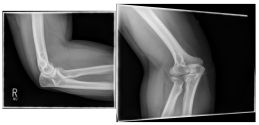

Ellenbogen2

Photo: A fracture with several framents